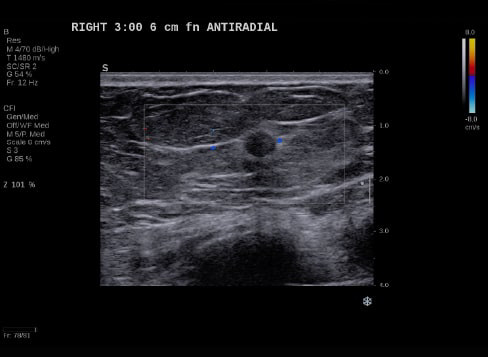

Case Example 1:

77-year-old female recalled for diagnostic imaging on new 0.7 cm mass seen on right breast. Ultrasound imaging demonstrates a round mass with an echogenic rim and minimal doppler signal.

Case Example 1: Observations

With OA, we can see deoxygenated hemoglobin both internally to the mass and externally in the boundary and periphery of the mass as an intense pink blush as it invades normal breast tissues.

On the combined map (upper middle) and relative map (lower middle), and even in the total hemoglobin map (lower left), we can see perpendicular vessels in the peripheral zone that enter through the boundary zone. These are characteristics seen in cancerous masses.

Invasive Breast Carcinoma Grade II – with Lobular Feature

- ER+

- HER2-

- PR+

- Ki67=15%

This patient was up-classified to a BI-RADS 5. Luminal B masses typically present with both internal and external OA features.